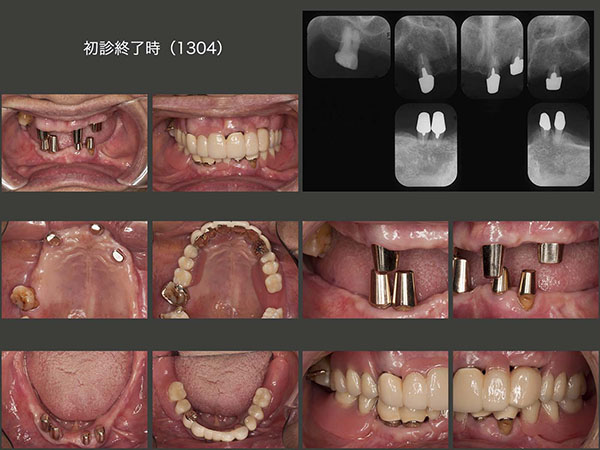

4.移植でやり繰りし、義歯を回避

2009年2月初診,26歳の女性.主訴は義歯を入れて欲しい.とにかく歯医者嫌いで恐怖心が強い.そうでなければここまで放置しないはずである.幼児期に治療を受けた嫌な思い出がトラウマになって歯医者にかかれない人は結構いると思われる.勇気を振り絞って来院したことをまずは褒め,とにかく信頼関係の構築に主眼を置き,徐々に治療を行っていった.右下の残根を抜歯し,そこに義歯を装着することは簡単だが,右下犬歯にクラスプが見えるのは審美的に耐えられないであろう.それでは,インプラントを用いるかといっても,費用が高く経済的に厳しい.

そこでまず,10年3月に左上7の残根を抜歯し,口蓋根のみを再植した.つぎに右上7を分割抜歯したところ,3根ともに歯根膜が付着しており,条件が良かった.そこで,それぞれを右下に移植した.なお右下7は,根長が短くさすがに保存できず,この症例で唯一抜歯となった歯である.抜歯後の顎堤が細かったが,3根を一直線に並べることで対応できた.

残りの治療を行い,初診から3年4ヵ月を費やし,何とか治療を終了することができた.

初診時と初診終了後約1年のパノラマX線写真の比較(妊娠したため,初診終了時のパノラマX線写真は撮らず).私自身も治療結果には満足している.しかし,問題はその後である.患者さんは最初の1回,リコールに応じたが,その後は一度もリコールに応じてくれない.結婚し,子供が2人出来,仕事も常勤でこなし,とても忙しいとのことである.たまに近所で会うと,私が“一度見せてください” 彼女が“分かりました”とは言うもののもう5年,一度も来院されていない.口の中がどうなっているかとても心配であるが,本人が来てくれない限りどうしようもない.“歯”・“口”・“人”というが,つくづく“人”との関係が一番難しいと痛感する次第である.